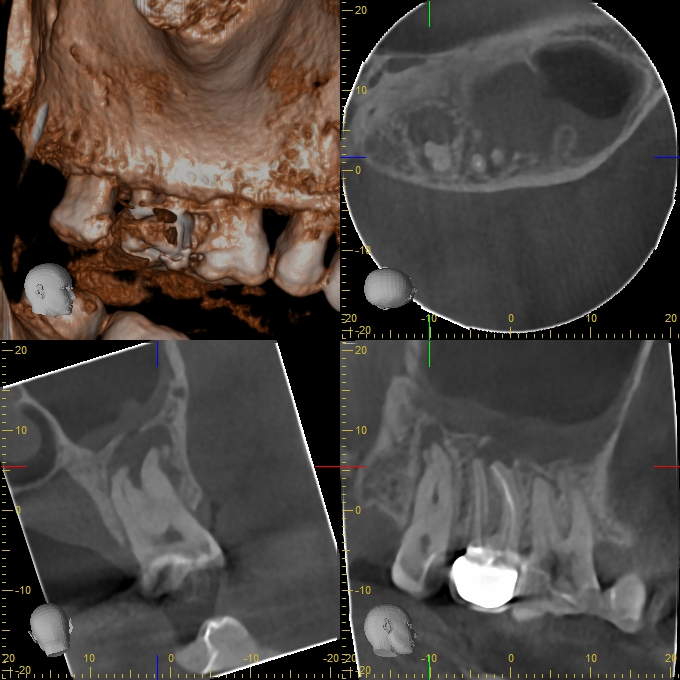

XYZView_20140429_111908

2D vs. 3D (XXVII)